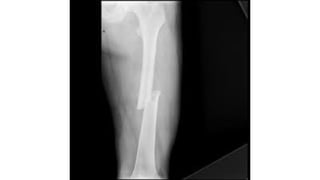

This document discusses femoral fractures, categorized by their location and severity, with classifications such as Garden classification. It outlines the types of fractures, including valgus impacted, non-displaced, partially displaced, and fully displaced, along with their surgical treatment options. Additionally, it briefly describes distal femur fractures, which occur just above the knee joint.